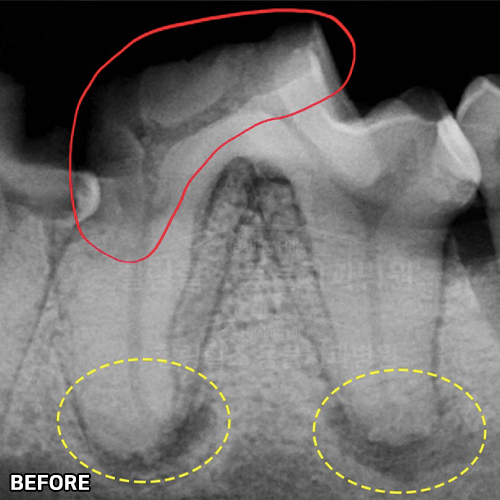

치아뿌리까지 파절된 강아지어금니 빨갛게 부어오른 잇몸치료~ 2년 뒤에 재생된 잇몸뼈 CT로 확인! 모든 동물병원에서 발치하자고 했지만 힐링힐스동물치과병원에서 되살려진 어금니!